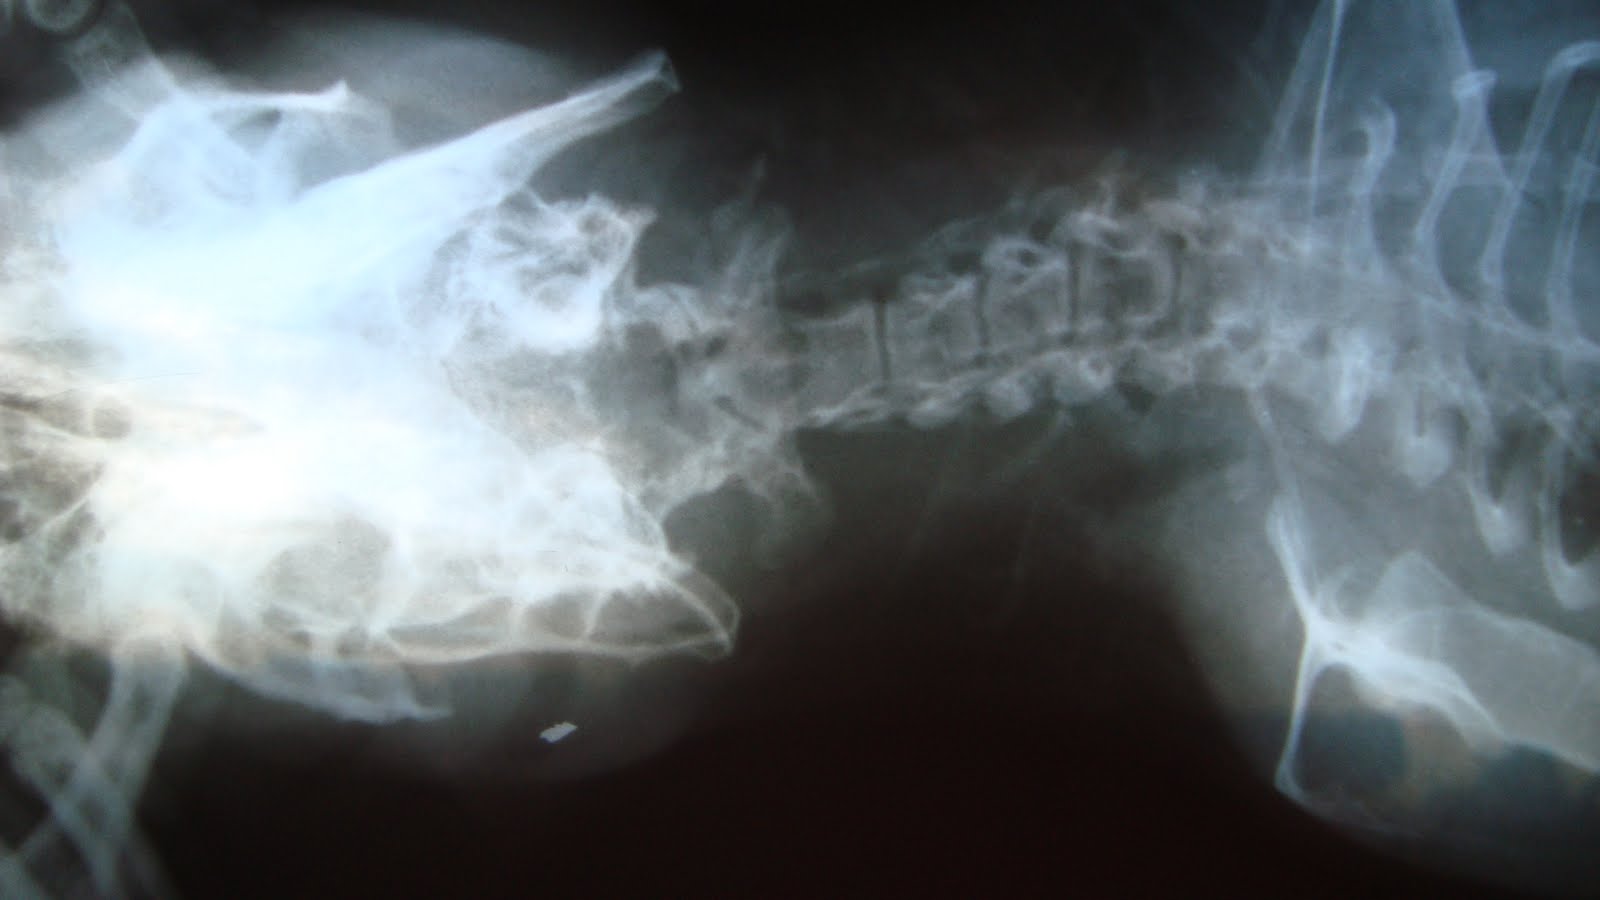

FRACTURE - RABBIT'S JAW

Poor rabbit got some injury and was not able to eat anything. Radiograph was done to find out the problem and his jaw was found fractured. Rest was best in this case. With time it will heal.

FRACTURED LEG OF BABY GUINEA PIG

This baby guinea pig was hurt by his father accidently which resulted in the fracture of the leg. He was making terrible noises because of pain and radiograph cleared the picture. The support has been given to the injured leg to restrict its movement. With time it should heal properly.